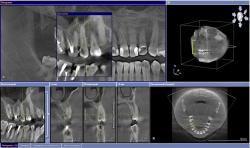

• Вопрос о необходимости эндодонтической терапии при наличии обширного кариозного поражения можно решить, проведя качественное диагностическое исследование с помощью челюстно-лицевого компьютерного томографа (рис. 47-50):

| Рис. 47 Фрагмент ортопантомограммы и фронтальный срез по оси, проведенной от вершины небного бугра к верхушке корня 1.5 зуба |

| Рис. 48-50 Профильные срезы через коронковую часть пульпарной камеры 1.5 зуба – небно: дистальная полость; фронтальный срез – вестибулярно: полость на медиальной поверхности |

• На основании 3D исследования, выявившего апроксимальные кариозные полости, затрагивающие пульпарную камеру, и на дистальной и на медиальной поверхностях 1.5 зуба, планируется эндодонтическое лечение.